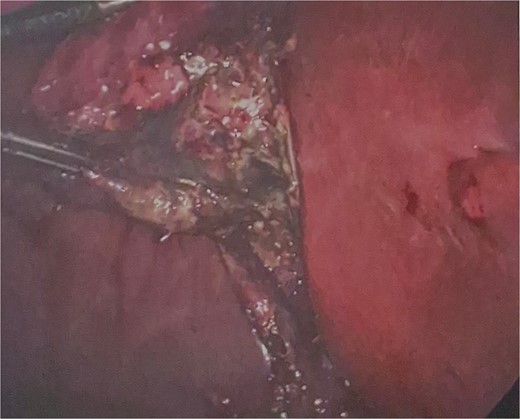

He was brought to theatre for a combined laparoscopic appendicectomy, drainage of peri-appendiceal abscess and cholecystectomy with intraoperative cholangiogram. Intraoperative findings included a 2 cm peri-appendiceal abscess cavity (Fig. 3) in keeping with pre-operative imaging. However, the gallbladder was gangrenous with a possible microperforation sealed by omentum (Fig. 4). Based on the intraoperative appearance, it was difficult to ascertain whether the abscess was due to primary appendicitis or whether the abscess was seeded from the cholecystitis and the appendix had become involved collaterally.

The cholecystectomy was performed first due to the evidence of gangrene. The gallbladder was decompressed, draining purulent bile, before dissection of the cystic duct and cystic artery to obtain the critical view of safety. Intraoperative cholangiogram was performed revealing a non-dilated biliary tree, clearly opacified upper ducts, no filling defects, and normal distal tapering with flow into duodenum. The gallbladder was dissected off the liver revealing a completely necrotic posterior wall.